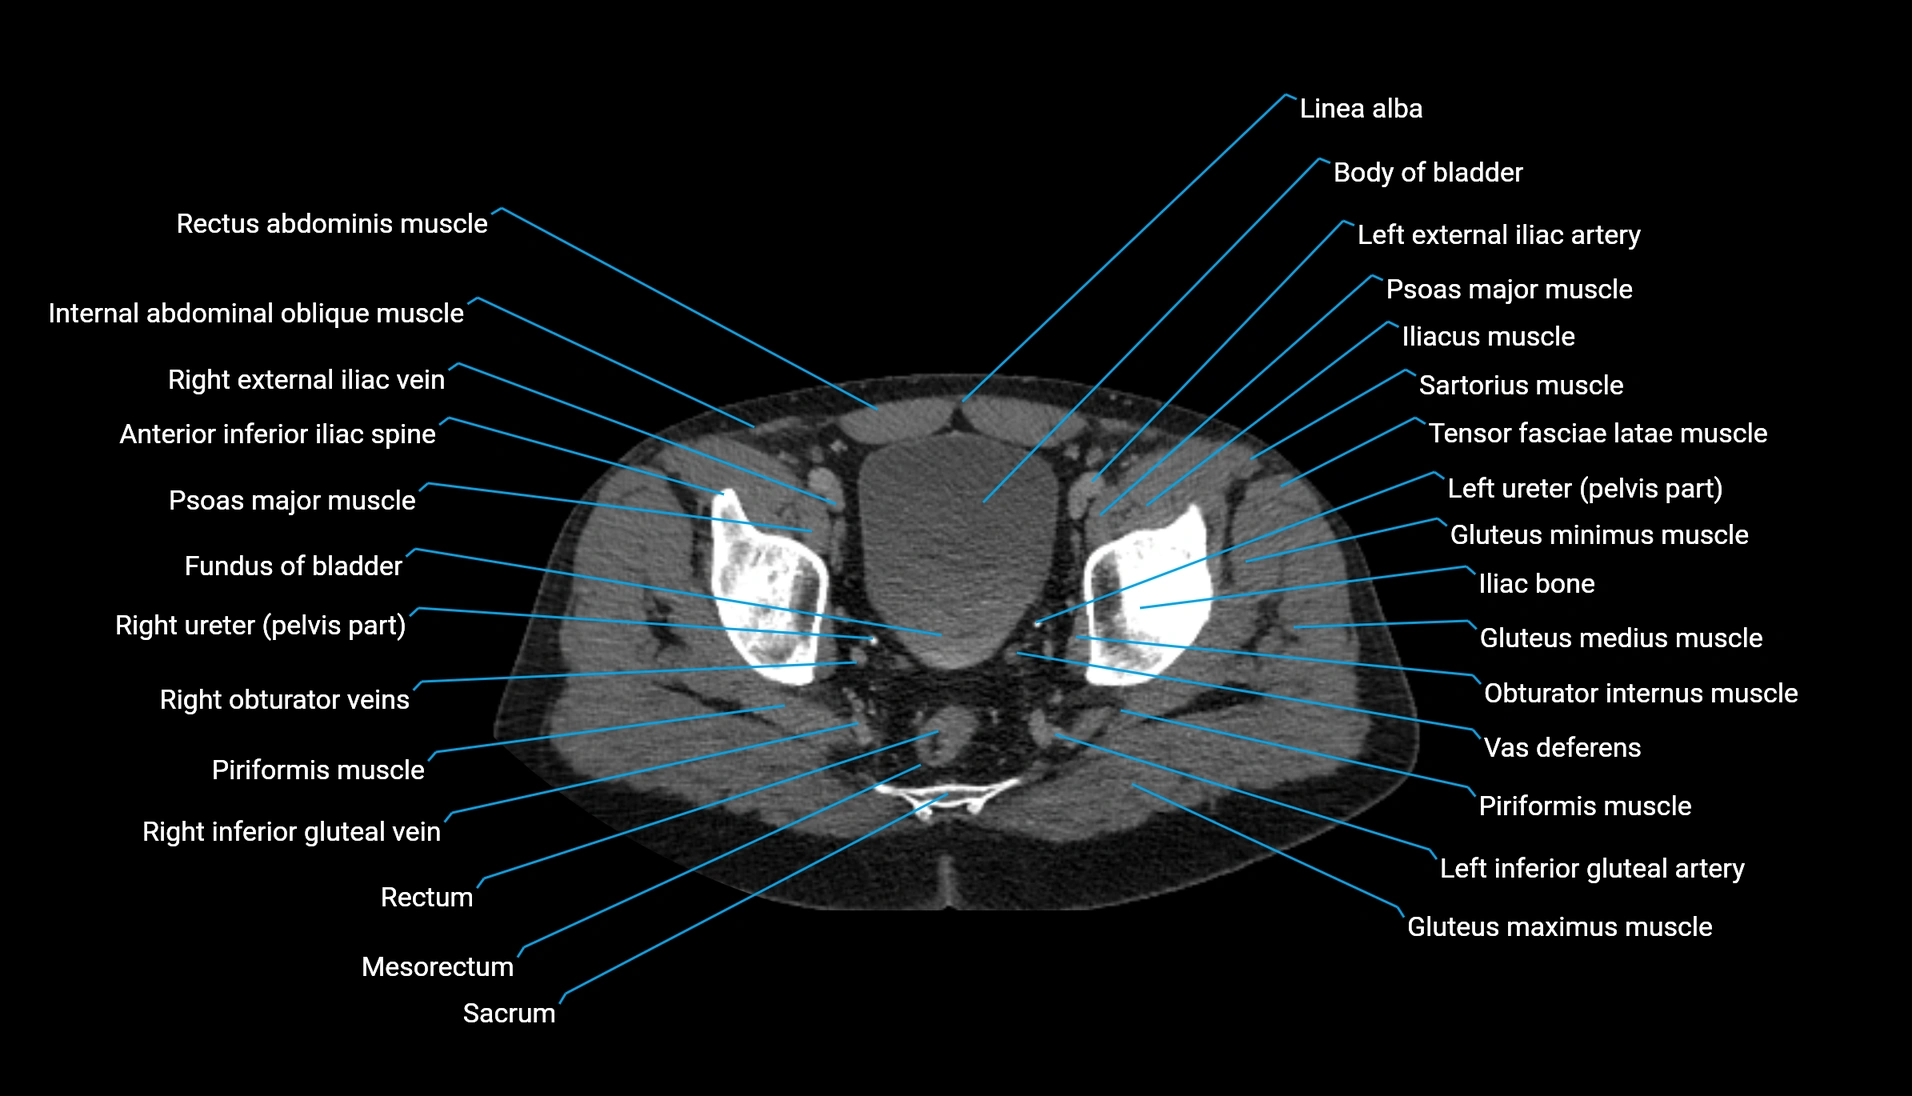

CT Appearance

Non-contrast CT:

-

Demonstrates cortical bone of acetabular rim in excellent detail

Detects fractures, dysplasia, retroversion, or bony overcoverage (pincer impingement)

3D reconstructions used in preoperative hip surgery planning

CT VRT 3D image

CT image